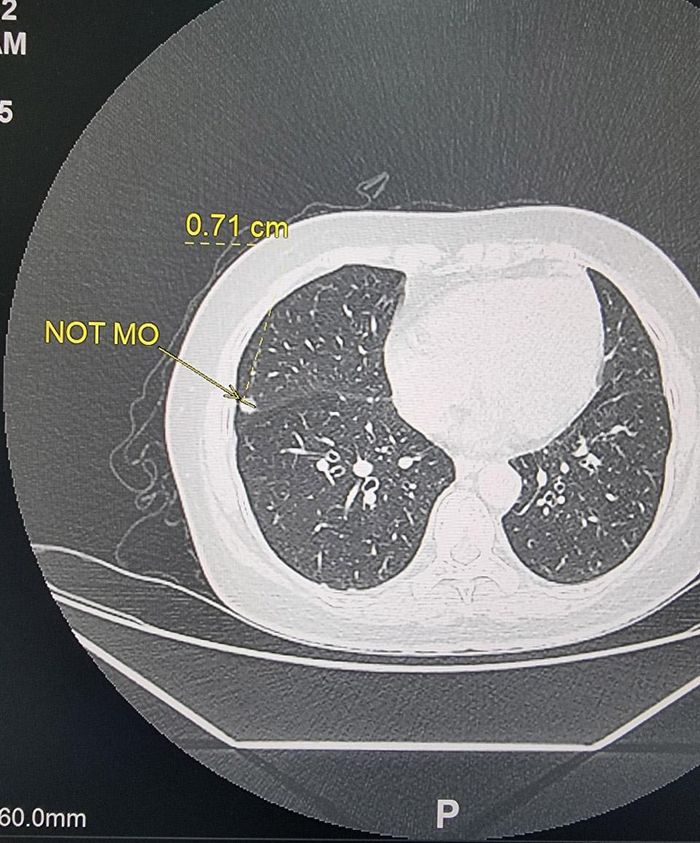

Người phụ nữ này cho hay, chồng bà gần đây đi khám sức khỏe được chẩn đoán mắc ung thư nên đã rất lo lắng. TS.BS Lâm chia sẻ, trên hình ảnh CLVT phát hiện bệnh nhân có nốt mờ nhỏ đường kính 7mm nằm ở thùy giữa phổi phải cách màng phổi thành ngực bên 5mm.

Hình ảnh nốt mờ dưới màng phổi nghi ngờ khối u của bệnh nhân. Ảnh: Bác sĩ cung cấp

“Vấn đề khó khăn với phẫu thuật viên là nốt mờ nằm dưới màng phổi không thể quan sát trực tiếp vị trí qua hình ảnh nội soi. Với nốt mờ nhỏ đường kính 7 mm lại nằm sau xương sườn gần sát màng phổi, nếu dùng kỹ thuật sinh thiết xuyên thành khả năng lấy được bệnh phẩm rất thấp, nguy cơ tràn khí và máu màng phổi cao”, TS.BS Lâm nói.